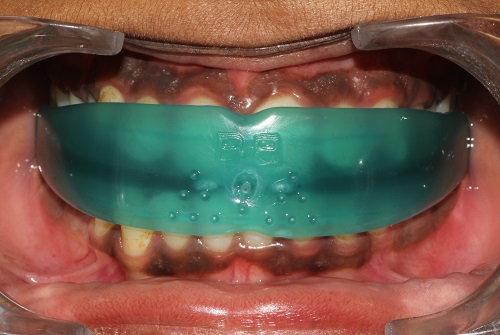

The various treatment offered in the department includes fixed orthodontic treatment with metal, ceramic,self-ligating brackets, treatment with mini-implants, Rapid Maxillary Expansion appliances, orthognathic surgeries to correct facial deformities, distraction osteogenesis procedures with Internal and External distractors, treatment of cleft lip and palate, Pre-surgical Naso Alveolar Moulding on cleft cases, Fixed functional treatment with Forsus, Powerscope, Herbst etc, Lingual Orthodontic treatment, Myofunctional Appliance Therapy, Aligner Orthodontic Treatment ,Myofunctional trainers, Splints- For Temporomandibular joint disorders as well as Class III correctors in growing individuals with appliances such as Tandem Traction Bow Appliance.